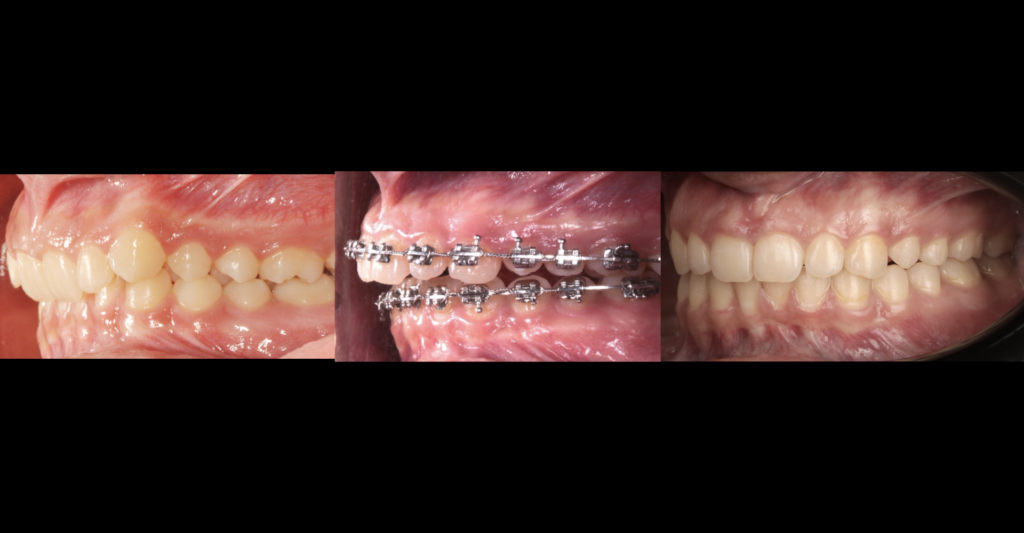

Debido a la maloclusion que presentaba, se le propuso a sus familiares el tratamiento de Ortodoncia (brackets) al terminar el tratamiento con guarda y terapia articular; posterior a los picos de crecimiento comenzó la fase activa de la asimetría, y después de realizar el estudio de los elementos diagnosticos como tomografía dental, radiografias, fotografías y gammagrafias, el caso fue planeado desde un principio con el objetivo de prepararlo para realizar cirugía Ortognatica al finalizar su desarrollo facial.

Trabajando siempre en contacto con el servicio de Cirugía Ortognatica, se llegó a la etapa donde ya se podría realizar la corrección quirúrgica y se hicieron los últimos ajustes para obtener el mejor resultado, posterior al procedimiento quirúrgico los resultados funcionales y estéticos fueron los ideales, así la paciente ahora presenta una estética facial y dental harmoniosa y funcionalmente puede masticar y hablar sin dolor alguno.

Paciente con hiperplasia de rama mandibular unilateral derecha, tratada mediante ortodoncia y cirugía ortognática. Presentaba dolor, ruidos articulares y dificultad para masticar. Tras planificación con estudios radiográficos y tomográficos, se realizó corrección quirúrgica logrando estética facial armónica y función oral sin dolor.